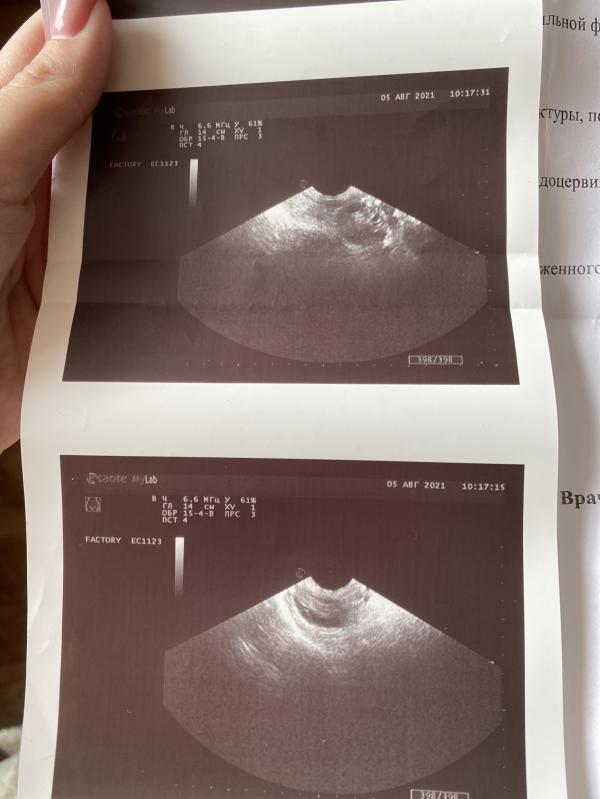

Яичники с мелкими фолликулами, без четко выраженного доминирующего фолликула.

Как же я устала слышать это на каждом Узи.

Все 8 месяцев, как я стала ежемесячно делать Узи, у меня ни разу не было доминантных фолликулов, на стимуляции я думала будет другая ситуация.

Что сказала мне врач?

Сказала, что я рано пришла, сказала, что это всего лишь первая стимуляция и на ней может не выйти. Приходи на 18 ДЦ.